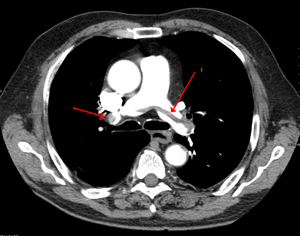

Segmental and subsegmental pulmonary emboli on both sides

CT pulmonary angiography showing a "saddle embolus" at the bifurcation of the main pulmonary artery and thrombus burden in the lobar arteries on both sides.

التصوير الطبقي المحوسب

التصوير الطبقي المحوسب للرئة والمصحوب باستخدام الصبغة المشعة في الوريد أصبح واسع الانتشار والاستخدام في تشخيص المرضى المشتبه بإصابتهم بالانصمام الرئوي، لهذا النوع من التصوير حساسية تبلغ 83% ودقة نوعية تصل إلى 96%.[24].[25]